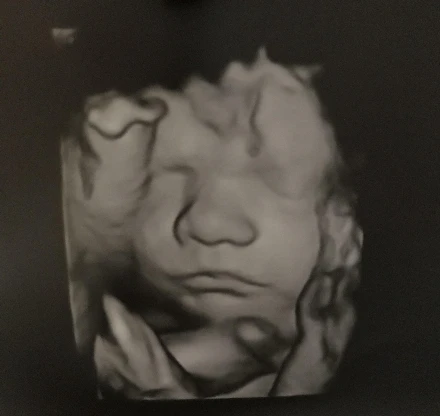

Az elmúlt héten töltöttem be a 30 hetet, így aktuálissá vált ismét egy nagyobb ultrahang. Nagyon izgultam előtte, hiszen az első babánkkal ez volt az utolsó vizsgálat, amin jártunk és ott még minden rendben volt.